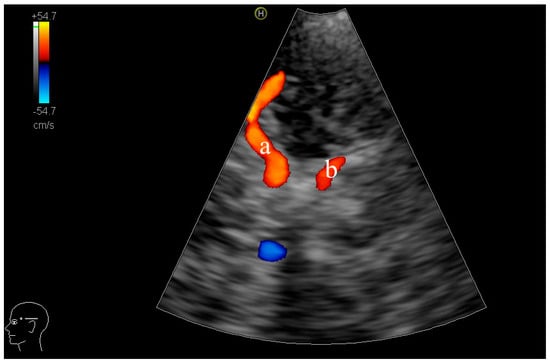

2.3. TCCD Examination Procedure

- Frid, P.E.; Schreiber, S.J.; Pade, O.; Doepp, F.; Valdueza, J. The Posterior Cerebral Artery and Its Main Cortical Branches Identified with Noninvasive Transcranial Color-Coded Duplex Sonography. Ultrasound Int. Open 2015, 1, E53–E57. [Google Scholar] [CrossRef]